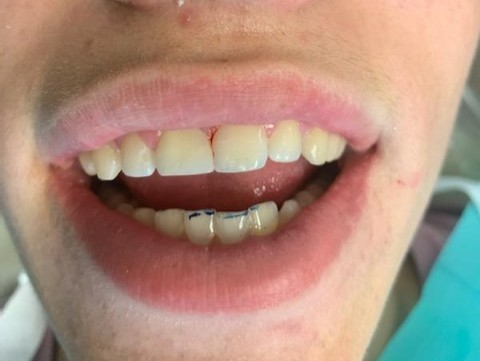

2

Anterior broken tooth. Double DentXpinTM repair.

3